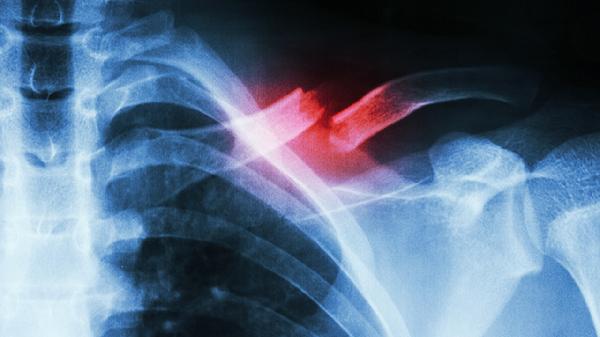

肋骨骨折了晚上睡觉疼得厉害怎么办

肋骨骨折夜间疼痛明显可通过药物镇痛、体位调整、呼吸训练、物理治疗、心理疏导等方式缓解。肋骨骨折多由外力撞击、骨质疏松、剧烈咳嗽等因素引起,疼痛程度与骨折数量、位置及个人耐受性相关。

肋骨骨折恢复期需保持高蛋白饮食促进骨痂形成,每日摄入牛奶、鱼肉等优质蛋白。避免剧烈咳嗽及突然转身动作,睡眠时使用多个枕头支撑体位。定期复查X线观察愈合进度,若出现呼吸困难、发热等症状需立即就医。一般单根骨折需4-6周愈合,多根骨折可能延长至8-12周,老年患者或骨质疏松者恢复时间更长。